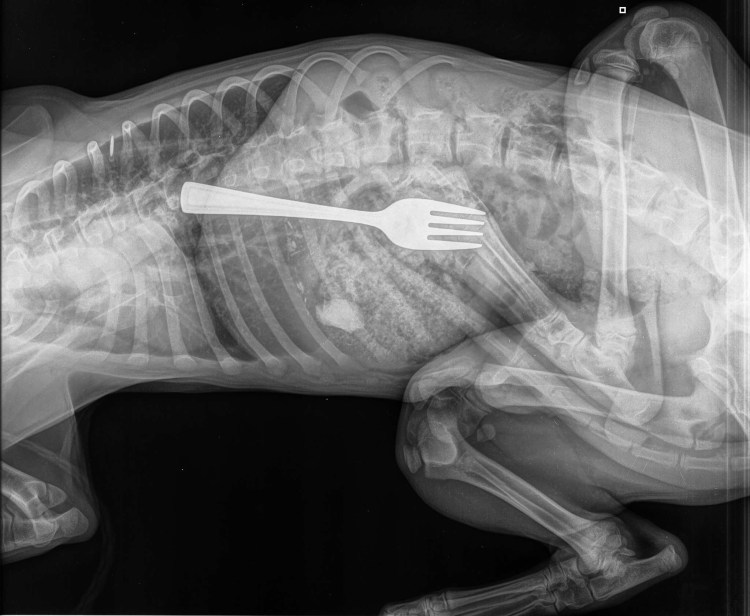

![Рентген собаки инородное тело]()

Рентген собаки инородное тело